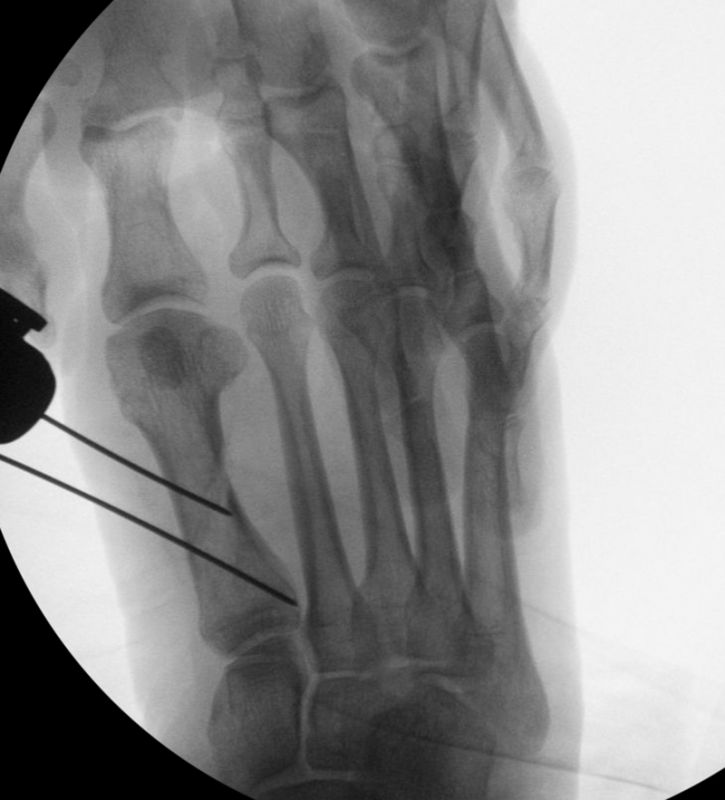

• Die Operationsplanung erfolgt anhand der Röntgenaufnahmen des Vorfußes unter Belastung in 2 Ebenen. Für die Verfahrenswahl sind wichtig der Intermetatarsalwinkel und die Breite des Os metatarsale, der Hallux valgus Winkel, der distalen Gelenkflächenwinkels (Distal Metatarsal Articular Angulation - DMAA), des Metatarsaleindex und Sesambeinposition (Abb. 1).

• Bildverstärker für intraoperative Kontrollaufnahmen 3.

• Bildverstärker.

• Kanülierte Schrauben bis 50 mm Länge, 4 mm Durchmesser, Beilagscheiben.

• Akkubohrmaschine, Kirschnerdrähte.

• Positionierung des Bildverstärkers im 90° Winkel zur Fußlängsachse (Abbildung 4).

Die Fräse wird auf eine Drehzahl von 3000 – 5000 RPM eingestellt.